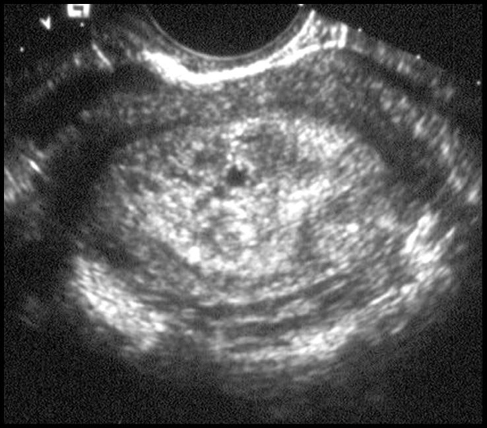

Rétention ovulaire